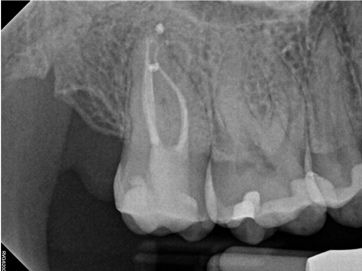

In the first case study, a young female patient was told she had a tooth (tooth No. 2, Figure 3) that should be extracted due to extensive bone loss. Using CBCT, the clinician was able to identify a large lateral canal within the palatal root. Despite the bone loss, the patient was eager to save her tooth. He offered to treat the tooth with the broad-spectrum acoustic technology. As shown in Figure 4, the preparation space was much smaller, which he was able to obturate efficiently. In addition, the small pinpoint of sealer in the middle of the palatal root indicated that the palatal lateral canal had been addressed (Figure 5). In the clinician's opinion, this area was likely the primary source of much of the bone loss.

Figure 6 through Figure 8 demonstrate that, 5 months after the procedure, complete healing had occurred, notably on the distal, where the probing had resolved to 2 mm. The patient then had a crown placed by her general dentist. Given her positive experience with the technology, she was eager to return as needed for continued follow-up.

Fig 3. Case 1: CBCT showed a large lateral canal within the palatal root (Fig 3). There was a small preparation space, which was efficiently obturated (Fig 4). A small pinpoint of sealer in the middle of the palatal root indicated that the palatal lateral canal had been addressed (Fig 5). After 5 months, CBCT demonstrated complete healing (Fig 6), notably on the distal, where probing had resolved to 2 mm. Radiographic images were taken immediately postoperatively (Fig 7) and 5 months postoperatively (Fig 8).

Fig 4. Case 1: CBCT showed a large lateral canal within the palatal root (Fig 3). There was a small preparation space, which was efficiently obturated (Fig 4). A small pinpoint of sealer in the middle of the palatal root indicated that the palatal lateral canal had been addressed (Fig 5). After 5 months, CBCT demonstrated complete healing (Fig 6), notably on the distal, where probing had resolved to 2 mm. Radiographic images were taken immediately postoperatively (Fig 7) and 5 months postoperatively (Fig 8).

Fig 5. Case 1: CBCT showed a large lateral canal within the palatal root (Fig 3). There was a small preparation space, which was efficiently obturated (Fig 4). A small pinpoint of sealer in the middle of the palatal root indicated that the palatal lateral canal had been addressed (Fig 5). After 5 months, CBCT demonstrated complete healing (Fig 6), notably on the distal, where probing had resolved to 2 mm. Radiographic images were taken immediately postoperatively (Fig 7) and 5 months postoperatively (Fig 8).

Fig 6. Case 1: CBCT showed a large lateral canal within the palatal root (Fig 3). There was a small preparation space, which was efficiently obturated (Fig 4). A small pinpoint of sealer in the middle of the palatal root indicated that the palatal lateral canal had been addressed (Fig 5). After 5 months, CBCT demonstrated complete healing (Fig 6), notably on the distal, where probing had resolved to 2 mm. Radiographic images were taken immediately postoperatively (Fig 7) and 5 months postoperatively (Fig 8).

Fig 7. Case 1: CBCT showed a large lateral canal within the palatal root (Fig 3). There was a small preparation space, which was efficiently obturated (Fig 4). A small pinpoint of sealer in the middle of the palatal root indicated that the palatal lateral canal had been addressed (Fig 5). After 5 months, CBCT demonstrated complete healing (Fig 6), notably on the distal, where probing had resolved to 2 mm. Radiographic images were taken immediately postoperatively (Fig 7) and 5 months postoperatively (Fig 8).

Fig 8. Case 1: CBCT showed a large lateral canal within the palatal root (Fig 3). There was a small preparation space, which was efficiently obturated (Fig 4). A small pinpoint of sealer in the middle of the palatal root indicated that the palatal lateral canal had been addressed (Fig 5). After 5 months, CBCT demonstrated complete healing (Fig 6), notably on the distal, where probing had resolved to 2 mm. Radiographic images were taken immediately postoperatively (Fig 7) and 5 months postoperatively (Fig 8).